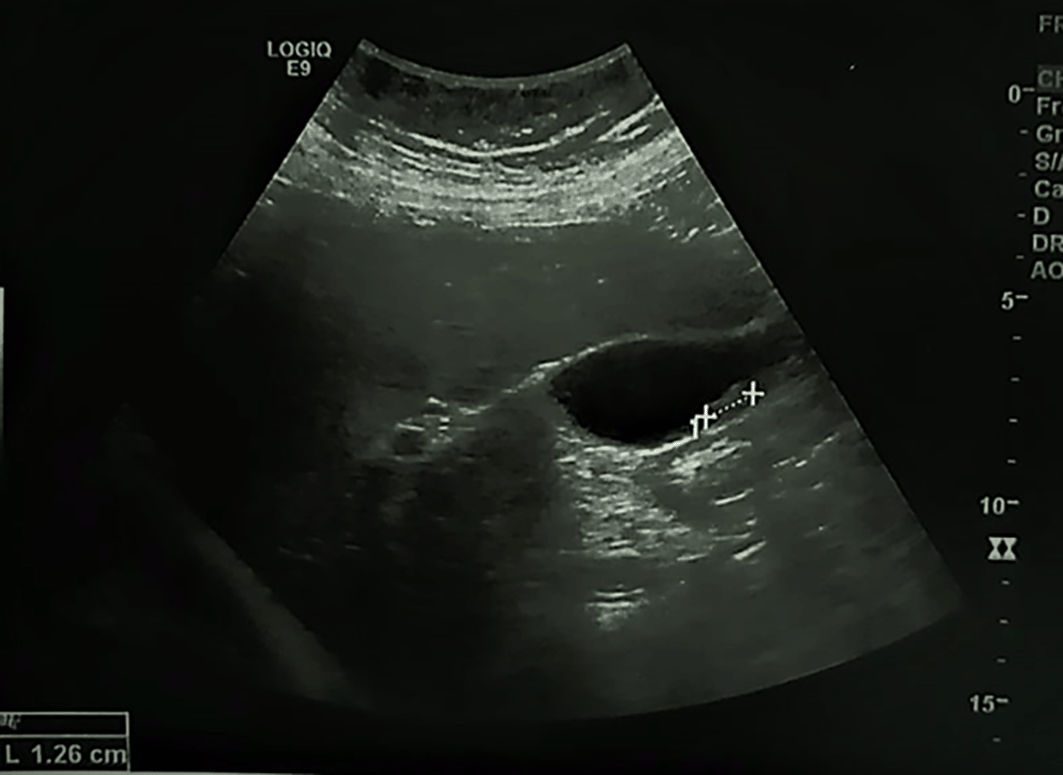

A 74-year-old postmenopausal woman, presented to the emergency department with fever and right upper abdominal pain. The patient, a Caucasian housewife, had no significant personal or family medical history. Physical examination on admission revealed tenderness and guarding of the right hypochondrium and a fever with a temperature of 38.2 degrees. Routine laboratory tests were normal except for a leucocytosis and an increased C-reactive protein (CRP) level. Abdominal ultrasonography showed a lithiasic gallbladder with thickened walls (see Figure 1). The patient was referred to the surgery department for cholecystectomy for acute lithiasic cholecystitis.

The walls of the gallbladder (GB) are thickened, hyperechoic with a mobile gallstone.